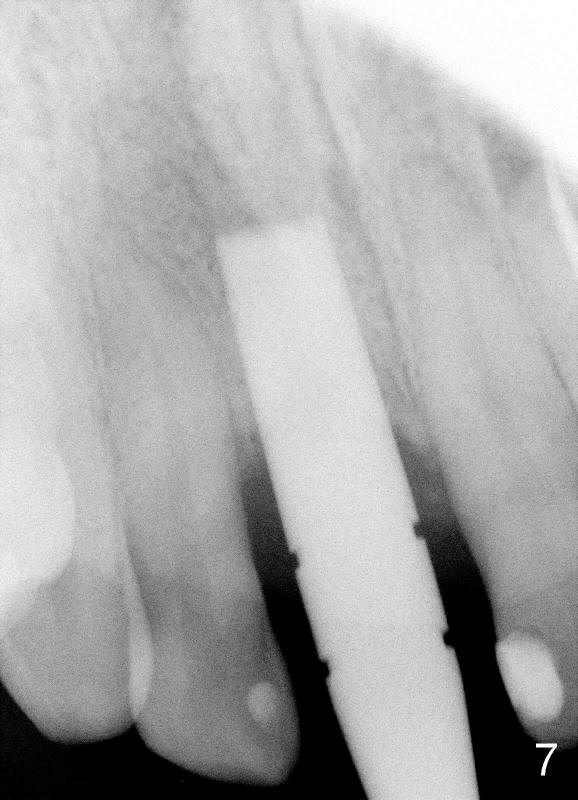

Two more weeks later, D2 implant (4.5x5.5x20 mm) is placed (Fig.9,10).  Fig.7 D2 thin socket former at ~ 16 mm depth, Fig.8 D2 medium socket former at ~ 19 mm.